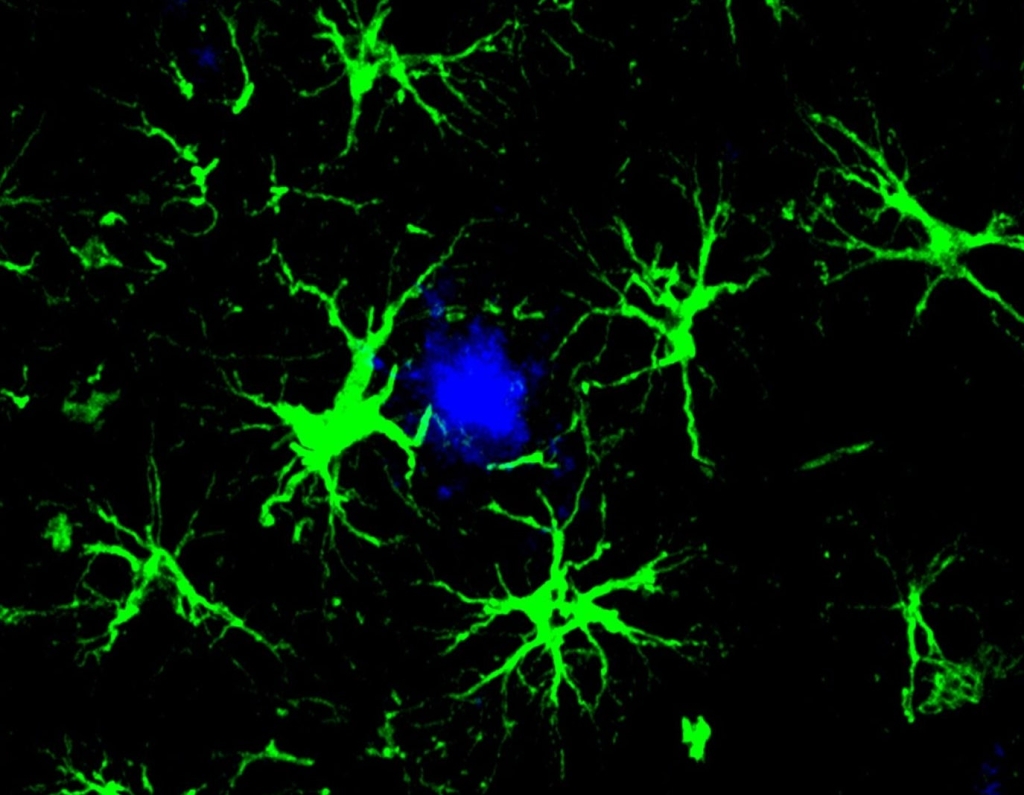

The researchers turned to astrocytes, the brain’s most abundant cell type. These star-shaped support cells help repair brain injuries, provide nutrients to neurons, and play crucial roles in memory and cognition. While astrocytes can naturally clear some proteins, they’re not particularly efficient at removing amyloid.

To boost their amyloid-clearing abilities, the team tested multiple CAR designs. They packaged the genetic instructions for the most promising designs into harmless viruses and injected them into mice modeling Alzheimer’s disease.

Once inside the brain, these viruses transformed naturally occurring astrocytes into CAR-A cells—astrocytes equipped with the ability to seek out and destroy amyloid proteins.

But the benefits extended beyond just clearing amyloid. The CAR-A cells also triggered the brain’s immune cells to more actively devour amyloid plaques, swept away malfunctioning immune cells, and reduced overall brain inflammation.